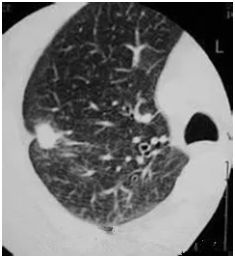

●高危結(jié)節(jié)

●結(jié)節(jié)呈毛栗子樣,周圍有角(棘突)和細(xì)小毛刺生長(zhǎng)

●結(jié)節(jié)如月亮,周圍有一圈暈

●結(jié)節(jié)呈分葉狀

●多位于上葉結(jié)節(jié)

●結(jié)節(jié)里有較粗的血管牽扯進(jìn)來(lái)

●結(jié)節(jié)里有透亮的小空泡(空氣支氣管征)

●結(jié)節(jié)外圍有胸膜牽拉征象(臍凹征)

●隨訪3—6月以上,結(jié)節(jié)明顯增大或內(nèi)部密度增高